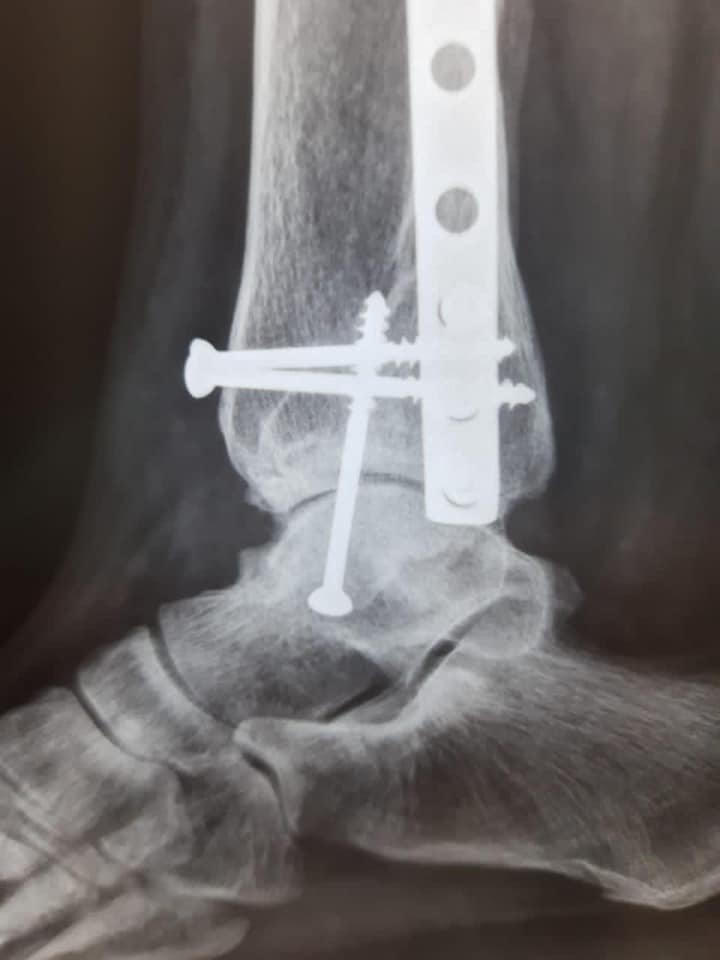

Essas são imagens de antes e depois feitas via Raio X onde foi realizado uma Artrodese de Tornozelo pelo

Doutor Luciano Moraes Brasil, Especialista em Pé e Tornozelo